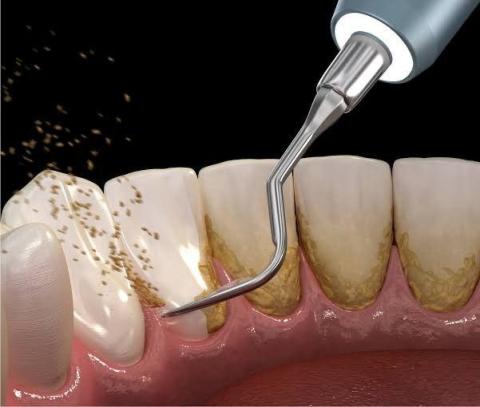

• Удаление зубного камня с помощью ультразвука;